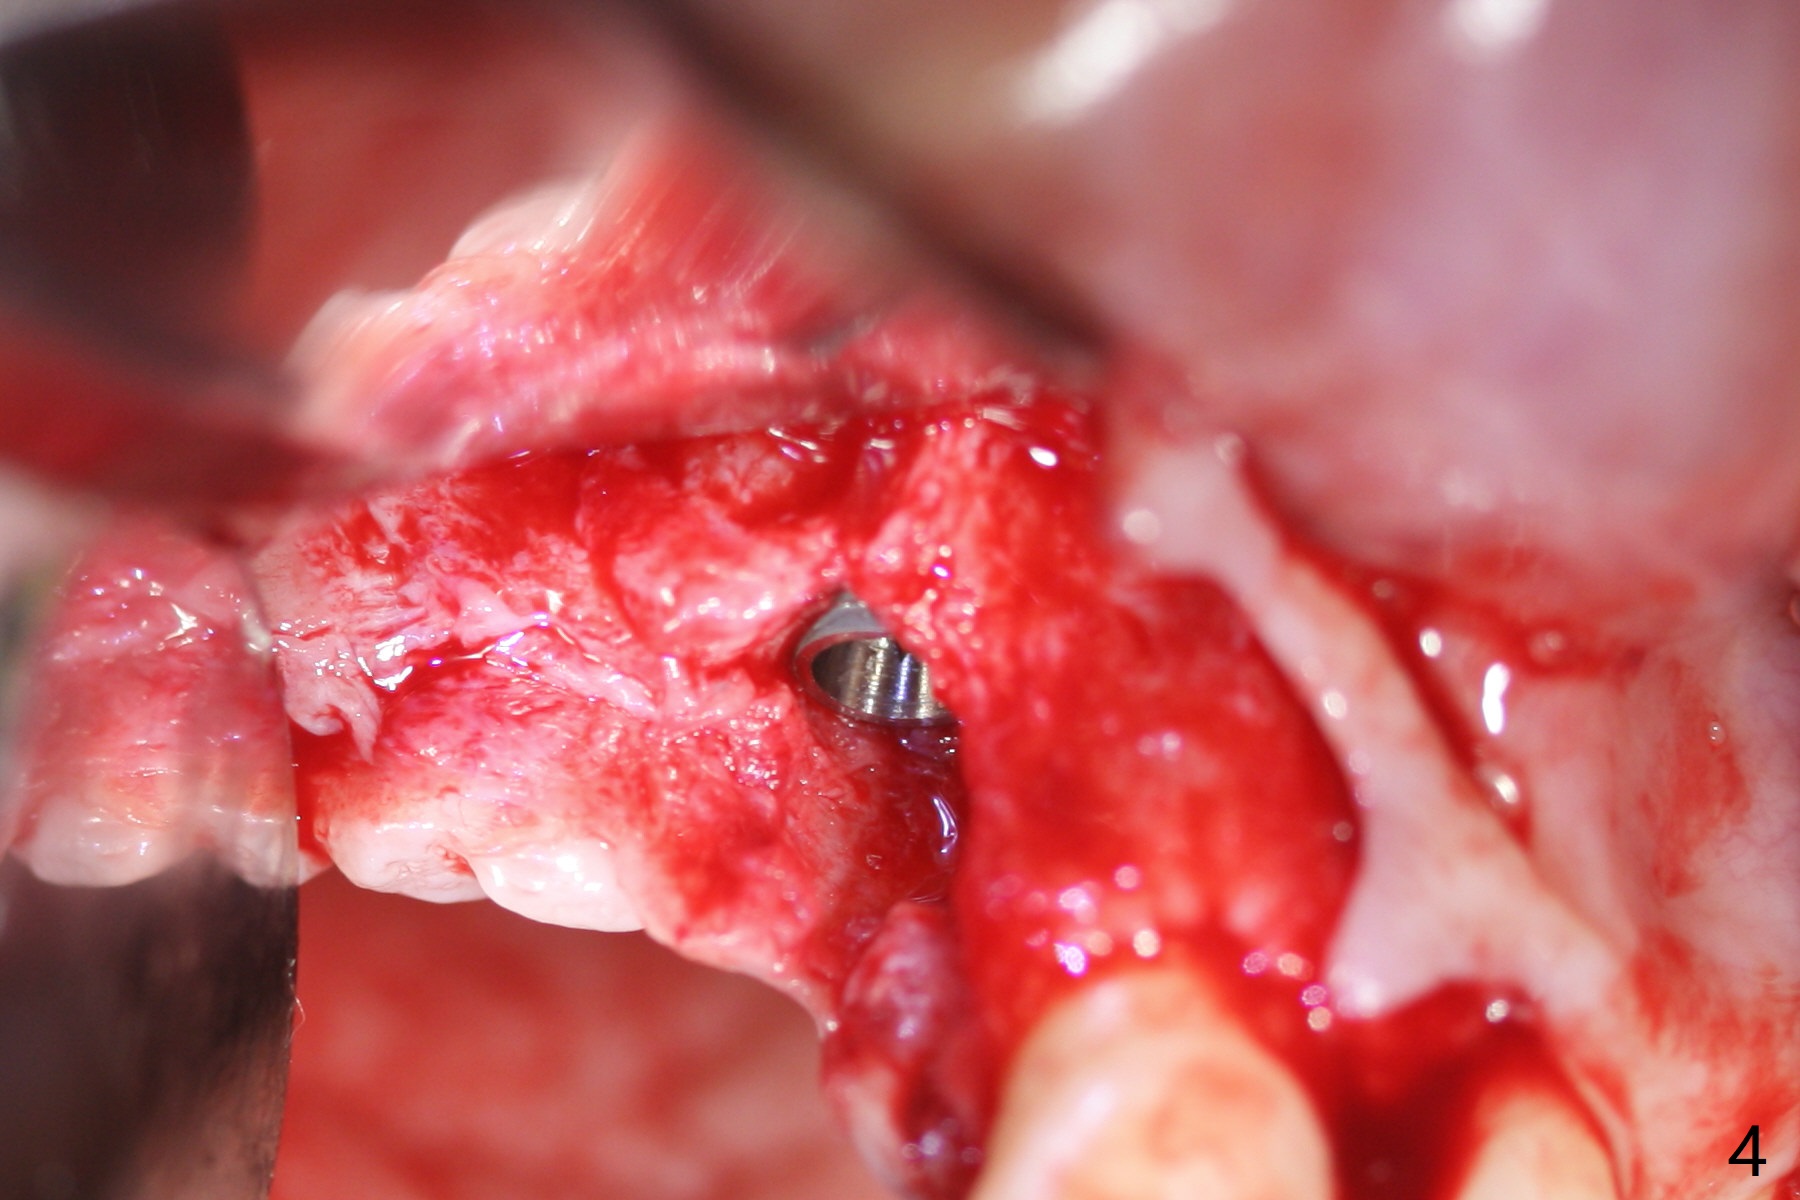

Eleven months post immediate implantation, the implant at #8 (4.5x16 mm, better smaller) is found to have thread exposure buccally (Fig.1) and distally (Fig.2). Immediately post implant removal, a 5x10 mm one is placed equi- or subcrestally distobuccally (Fig.3,4 (to prevent periimplantitis)). It is turned 4 more times later to make sure slightly supracrestally palatally, since the palatal crest is the lowest. After placement of sticky bone palatally, a 4.5(2) mm mill abutment is placed (17 mm long, Fig.5,6). The buccal flap is raised until the anterior nasal (Fig.5 N) foramen. After severing the periosteum and placement of 2 of 8 mm tenting screws (Fig.7), sticky bone (Vanilla allograft/Osteogen; block graft denies) is applied at #6 and 7 sites (Fig.8). Following palatal flap separation, the wound is closed in an apparent tension free manner (Fig.9). Periodontal dressing is applied. After wound healing, lab-fabricated provisional is delivered.